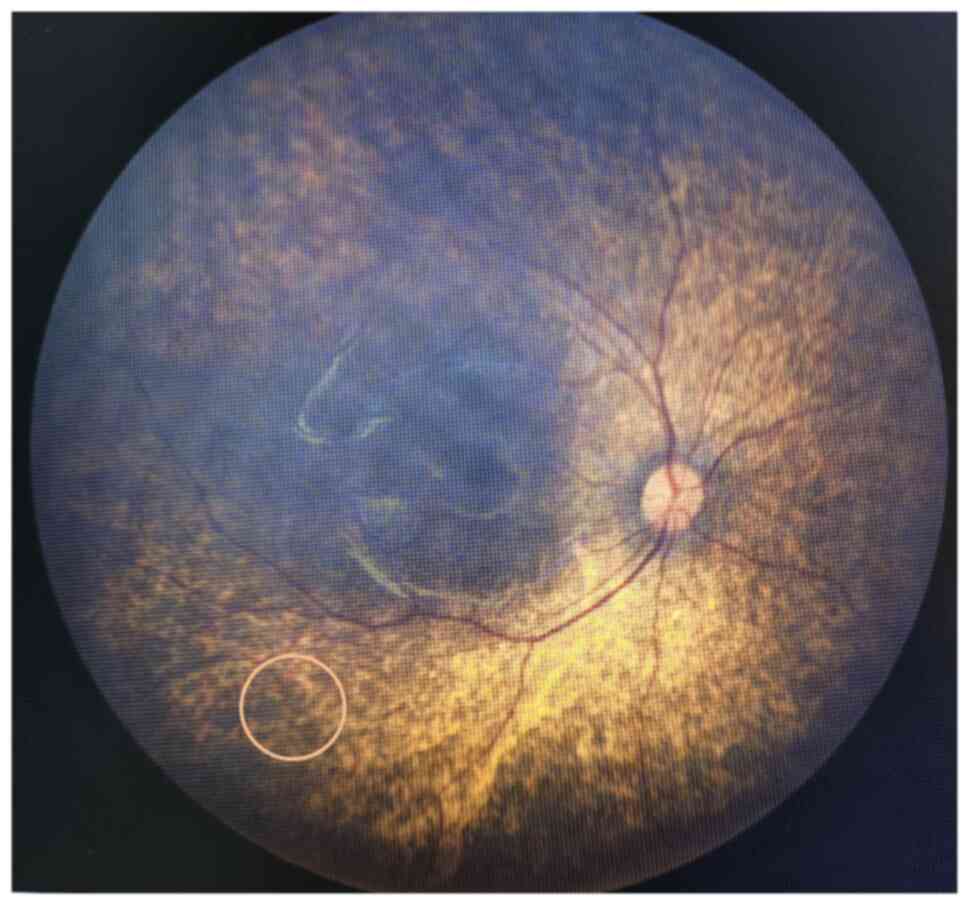

The patient exhibited a pale and weak appearance. Several palpable lymph nodes in the neck were detected by physical examination, with throat congestion and tonsil enlargement. The blood pressure was abnormal (140/80 mmHg), and a decreased hemoglobin level (68 g/l) and red blood cell count (2.35x1012/l) were detected on blood tests (Table I). Serum chemistry showed elevated serum creatinine (639 µM) and fasting plasma glucose (6.43 mM) levels (Table I), but other serum chemistry and immunological tests were normal. In addition, other abnormal data, including lower complement C3 and calcium levels, and higher urea, BNP and Troponin T, were also revealed by serum chemistry (Table I). Urine tests showed proteinuria (2+) and positive urine glucose (+), but hematuria was ruled out by microscopy. Abdominal ultrasound examination with a Philips EPIQ5 (Probe model C5-1; Philips Medical Systems, Inc.; Table SI) revealed that both kidneys were 53x23 mm, with hyperechogenicity and an unclear boundary between the cortex and medulla. According to the guidance of a nephrologist, this patient was diagnosed with stage 5 chronic kidney disease (Kidney Disease: Improving Global Outcomes guidelines), which was a contraindication for a renal biopsy. Increased liver echogenicity, intrahepatic bile duct dilation and splenomegaly were also detected. Cardiac ultrasound showed congenital heart disease, with left ventricular enlargement and mild mitral insufficiency. In addition, visional impairment had been noticed in the previous admission to Xinhua Hospital Affiliated to Shanghai Jiao Tong University School of Medicine. Therefore, a fundus camera was now used to collect high-resolution images of the fundus, which can be accurately obtained in a short time without mydriasis. Bilateral RP was confirmed, but OA was not evident (Fig. 1). Based on these findings, a diagnosis of renal failure, moderate ammonia and congenital heart disease was considered. Simultaneously, a diagnosis of WS1 was also suspected, as an abnormal plasma glucose level and RP had been found.

Figure 1

Bilateral retinitis pigmentosa was detected by fundus photography. The circle indicates osteocytoid pigmentation.